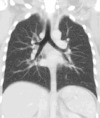

Lungs

A CT scan can be used for detecting both acute and chronic changes in the lung parenchyma, the tissue of the lungs. It is particularly relevant here because normal two-dimensional X-rays do not show such defects. A variety of techniques are used, depending on the suspected abnormality. For evaluation of chronic interstitial processes such as emphysema, and fibrosis, thin sections with high spatial frequency reconstructions are used; often scans are performed both on inspiration and expiration. This special technique is called high resolution CT that produces a sampling of the lung, and not continuous images.

Bronchial wall thickening can be seen on lung CTs and generally (but not always) implies inflammation of the bronchi.[26] Normally, the ratio of the bronchial wall thickness and the bronchial diameter is between 0.17 and 0.23.[27]

An incidentally found nodule in the absence of symptoms (sometimes referred to as an incidentaloma) may raise concerns that it might represent a tumor, either benign or malignant.[28] Perhaps persuaded by fear, patients and doctors sometimes agree to an intensive schedule of CT scans, sometimes up to every three months and beyond the recommended guidelines, in an attempt to do surveillance on the nodules.[29] However, established guidelines advise that patients without a prior history of cancer and whose solid nodules have not grown over a two-year period are unlikely to have any malignant cancer.[29] For this reason, and because no research provides supporting evidence that intensive surveillance gives better outcomes, and because of risks associated with having CT scans, patients should not receive CT screening in excess of those recommended by established guidelines.[29]